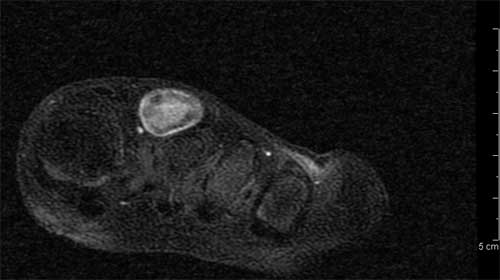

Figura 6.Ricostruzione MIP. In questa breve sequenza di immagini si pu� notare il passaggio dal lume vascolare normale alla porzione ectasica e quindi di nuovo al calibro regolare (Figura 7). ![]() ![]() ![]() ![]() ![]() ![]() |

Figura 7. Serie di tomogrammi assiali STIR. L�intervento � stato condotto con l�induzione di una breve anestesia generale e l�escissione completa della formazione (Figura 8, 9 e 10).